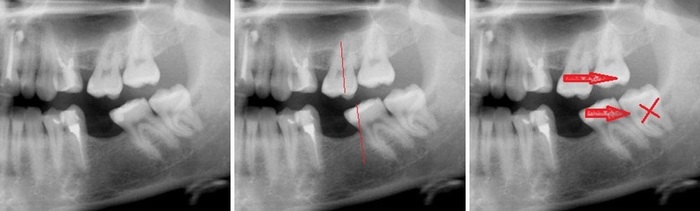

Горизонтальный – зуб мудрости, черная полоска под ним – нижнечелюстной нерв.

Открываю я снимок и вижу, что действительно так и было:

Черная полоска, уходящая в правый нижний угол картинки, отмеченная кружком, и есть то место, где был перебит нерв.